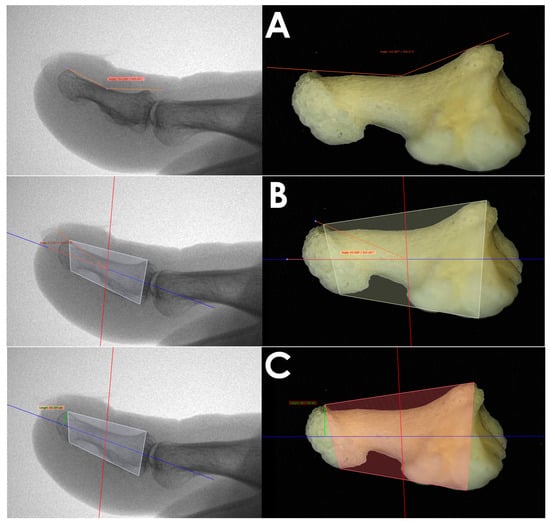

Dorsal curvature of the distal phalanx (DCDP) (orange line): the distance between the highest proximal-dorsal point and the highest distal-dorsal point, as well as the lowest point on the foot sole of the phalanx diaphysis (Figure 1A).

Distal phalanx hyperextension angle (DPHA) (orange line): the angle formed by the mid-axis of the distal phalanx and the highest point of the distal phalanx (Figure 1B).

Height of dorsal osteophyte (HDO) [11] (green line): the distance from the peak of the exostosis at 90° to the mid-axis of the phalanx (Figure 1C).

Figure 1. Left—Radiological measurements; right—Bone imaging of anatomical dissections. Measurements analyzed: (A) DCDP, (B) DPHA, (C) HDO.